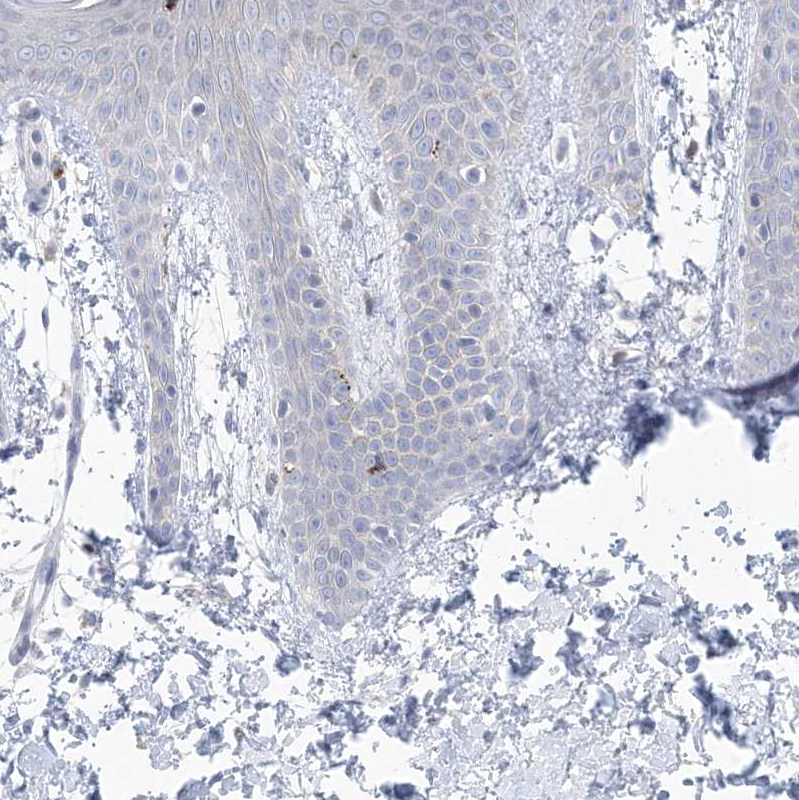

Immunohistochemical staining of human Cerebral cortex shows strong membranous and cytoplasmic positivity in neuronal cells.